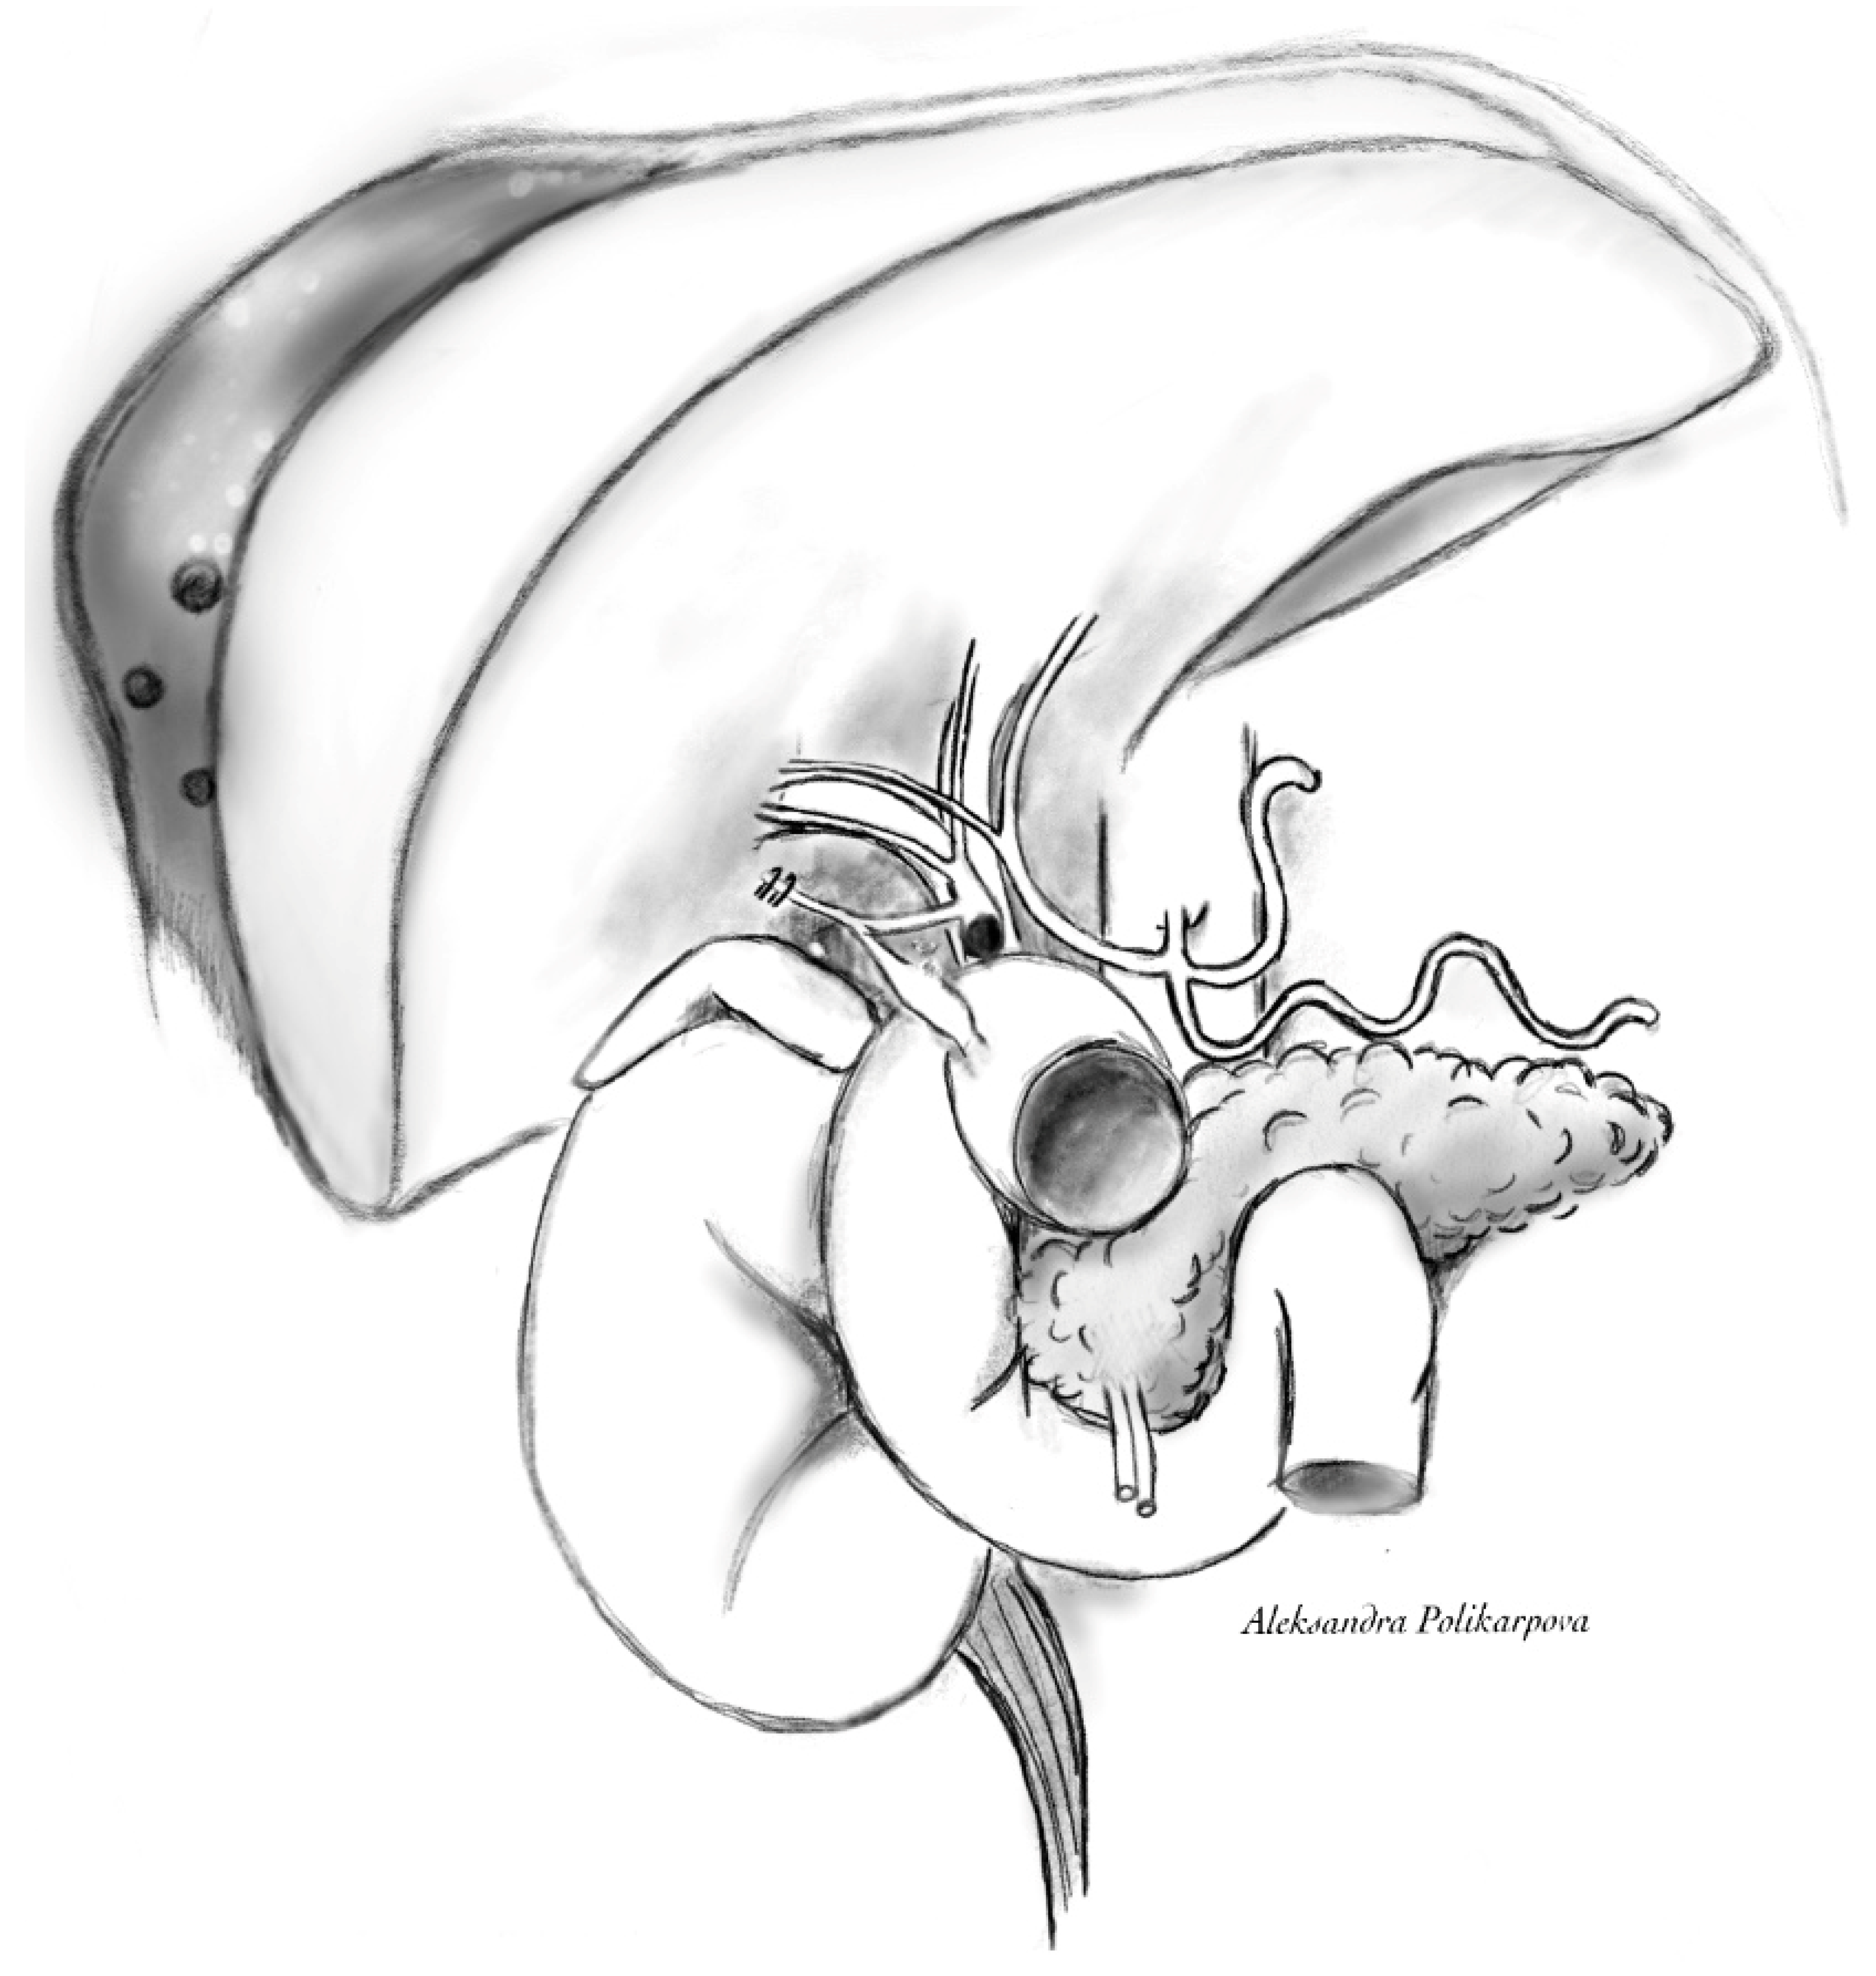

Figure 2.

Cystic duct remnant—duodenal fistula, retained CBD stone and collection adjacent to segments 6 and 7. Schematic drawing.